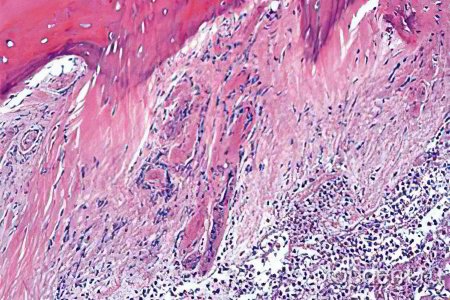

Остеомиелит — это инфекционное воспаление всех элементов костной ткани, включая кость, надкостницу и костный мозг. При этом поражается не только кость, но и костный мозг, который увеличивается и отекает. Жесткая оболочка начинает давить на окружающие ткани, что приводит к сжатию кровеносных сосудов и нарушению кровоснабжения в пораженной области. Это может вызвать разрушительные изменения. Если инфекция проникает за пределы кости, например, в мышечные ткани, может возникнуть абсцесс — скопление гноя в полости.

Прогрессирование болезни сопровождается образованием мелких кровоизлияний, вызванных тромбозом сосудов костной ткани. Это приводит к появлению гнойных очагов различного размера и вызывает отмирание отдельных участков тканей. Также могут возникать изолированные очаги некроза, что указывает на нозологические формы одонтогенного остеомиелита.